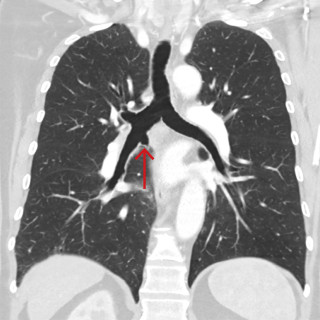

CT-bildene er fra en undersøkelse med opptak uten intravenøs kontrast. Bildet til venstre viser høy attenuasjon i myokard i venstre ventrikkel, og i mindre grad i høyre ventrikkel. Attenuasjonen er tilnærmet lik skjelett i bildet, og tettheten kan passe med forkalkninger. Opptaket er gjort på en spektral-CT, som har økt mulighet for å differensiere mellom ulike vevstyper. Maskinen utnytter de ulike energinivåene i røntgenstrålen, og den kan skille mellom grunnstoffer som jod og kalk utfra absorpsjonsnivået, da begge gir høy attenuasjon. Kalksuppresjon, vist på bildet til høyre (B), bekrefter...